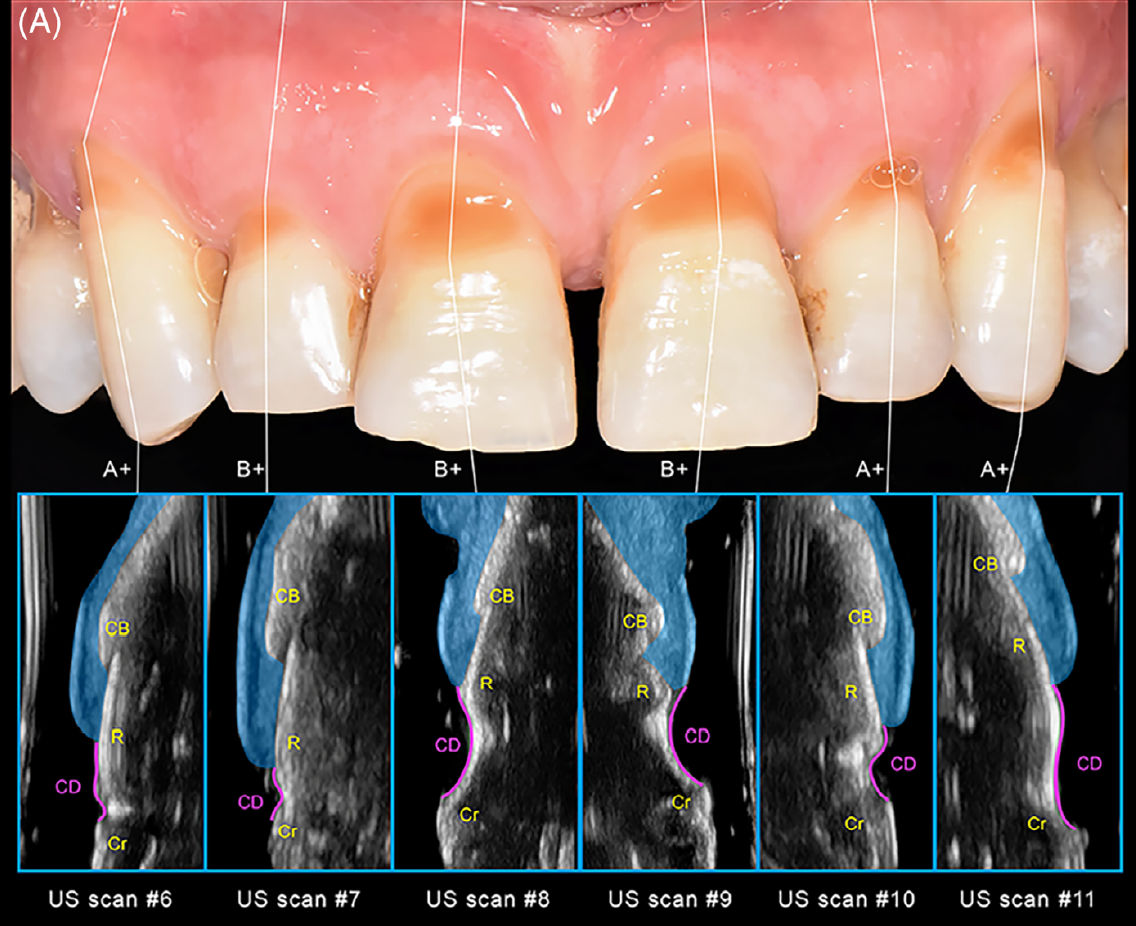

Рис 5. (A) Ультразвуковая характеристика пародонтальных структур передних зубов верхней челюсти с комбинированными дефектами (CD), включающими рецессии десны и NCCL.Нижние панели демонстрируют ультразвуковые (US) сканы, полученные в срединно-вестибулярной области передних верхнечелюстных зубов: «CB» — альвеолярный гребень кости; «CD» — зона комбинированного дефекта (включая NCCL и рецессию); «Cr» — клиническая коронка; «R» — корень.

Мягкотканный компонент выделен синим цветом. Все участки классифицированы как A+ или B+ (Pini Prato и соавт., 2010) из-за наличия клинически определяемых ступенек, что дополнительно подтверждено высокочастотной ультразвуковой визуализацией